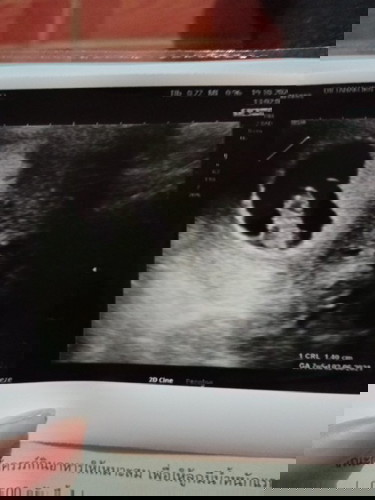

7W 5d หมอบอกว่าน้องแข็งแรงดี

เห็นแล้วดีใจมากคะ